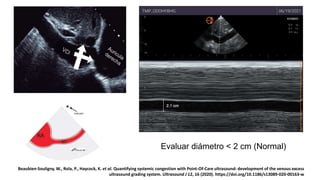

1.VCI

Evaluar diámetro < 2 cm (Normal)

Beaubien-Souligny, W., Rola, P., Haycock, K. et al. Quantifying systemic congestion with Point-Of-Care ultrasound: development of the venous excess

ultrasound grading system. Ultrasound J 12, 16 (2020). https://doi.org/10.1186/s13089-020-00163-w

1.VCI Evaluar diámetro <2 cm (Normal) Beaubien-Souligny, W., Rola, P., Haycock, K. et al. Quantifying systemic congestion with Point-Of-Care ultrasound: development of the venous excess ultrasound grading system. Ultrasound J 12, 16 (2020). https://doi.org/10.1186/s13089-020-00163-w